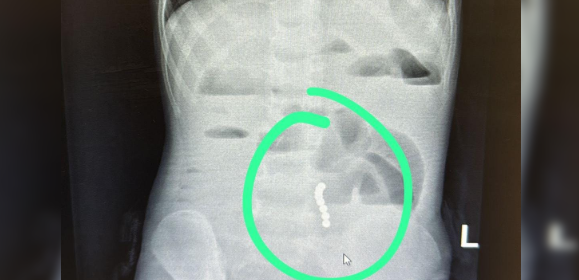

ד”ר ליאת יניב, רופאה בכירה במחלקת ילדים במרכז הרפואי בני ציון, זיהתה כי מדובר בהקאות ללא שלשולים ובעלות צבע חריג, ממצא שעורר חשד לבעיה משמעותית במערכת העיכול. בצילום הדמיה שבוצע בדחיפות, הודגמו מגנטים במעי הדק עם עדות לחסימת מעי.

בהתייעצות עם ד"ר ראוף נאסר, מומחה גסטרו ילדים, הפעוט הופנה להמשך טיפול כירורגי ונותח באופן דחוף ע"י ד”ר דניאל דובין, סגן מנהלת מחלקת כירורגיית ילדים במרכז הרפואי בני ציון ו ד"ר יאיר בן שמואל, רופא בכיר בכירורגיית ילדים, כאשר ד"ר אבו ראס עומר היה הרופא המרדים הבכיר. בניתוח הוצאו שמונה כדורי מגנט מהמעי הדק.